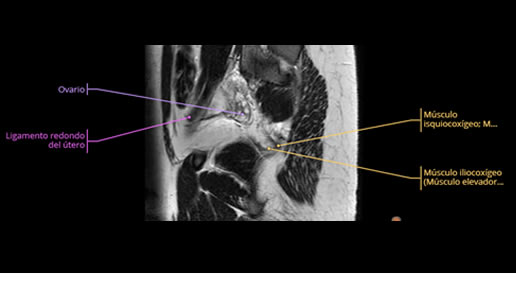

Se realizan adquisiciones en diferentes planos, con secuencias Spin echo y GRE, ponderadas a T1 y a T2, se utilizan pulsos de saturación de grasa y se administra medio de contraste a base de gadolinio.

El útero está en retroversión, retroflexión, y en posición central, se observa liquido en la cavidad endometrial, debido a la presencia de un Ca endometrial; en el anexo derecho se observa una masa quística que mide 3.8 x 2.2 cm de diámetro, corresponde a un quiste bilobulado, posee pared gruesa con componente solido puede tratarse de un Cistoadenocarcinoma, el cual realza con el medio de contraste de forma importante, entra dentro de una clasificación O-Rad tipo IV compatible con un Cistoadenocarcinoma